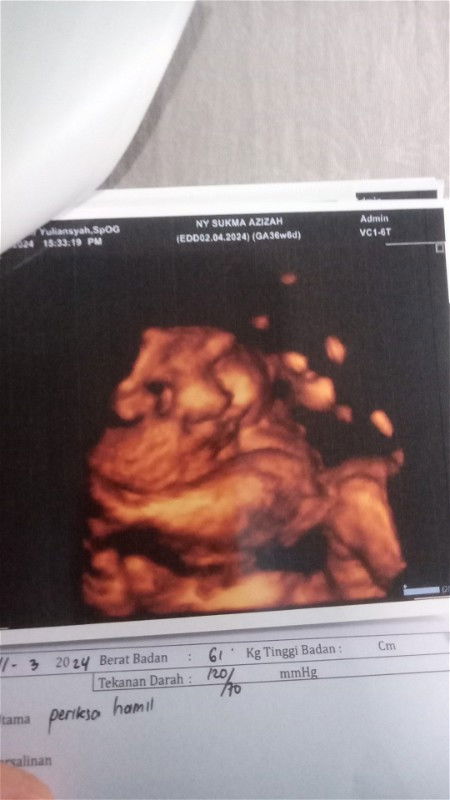

Alhamdulillah akhirnya bayi saya menampakkan wajah nya seneng bgt smua bagus ketuban cukup ,jernih , plasenta di atas,tidak ada lilitan tali pusar Masha Allah tabarakallah bbj 3kg ,gak sabar ketemu anakku, ada gak dsini bunda2 yg gak sabar ketemu pdhl udah bulan nya lahir 😀#Sharing_dong_Bund